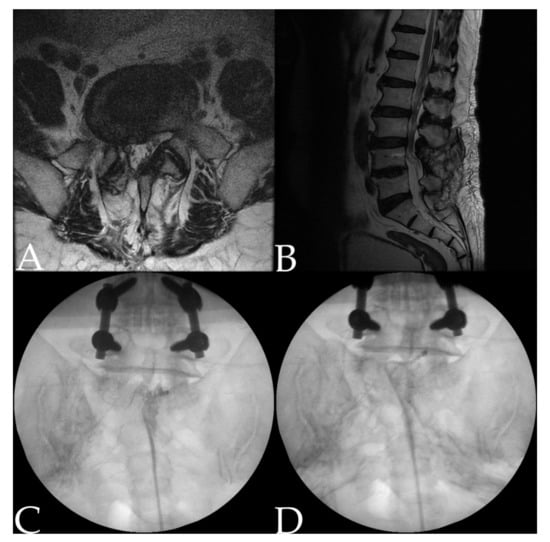

2.2. Procedure: Adhesiolysis Using a Steerable Catheter